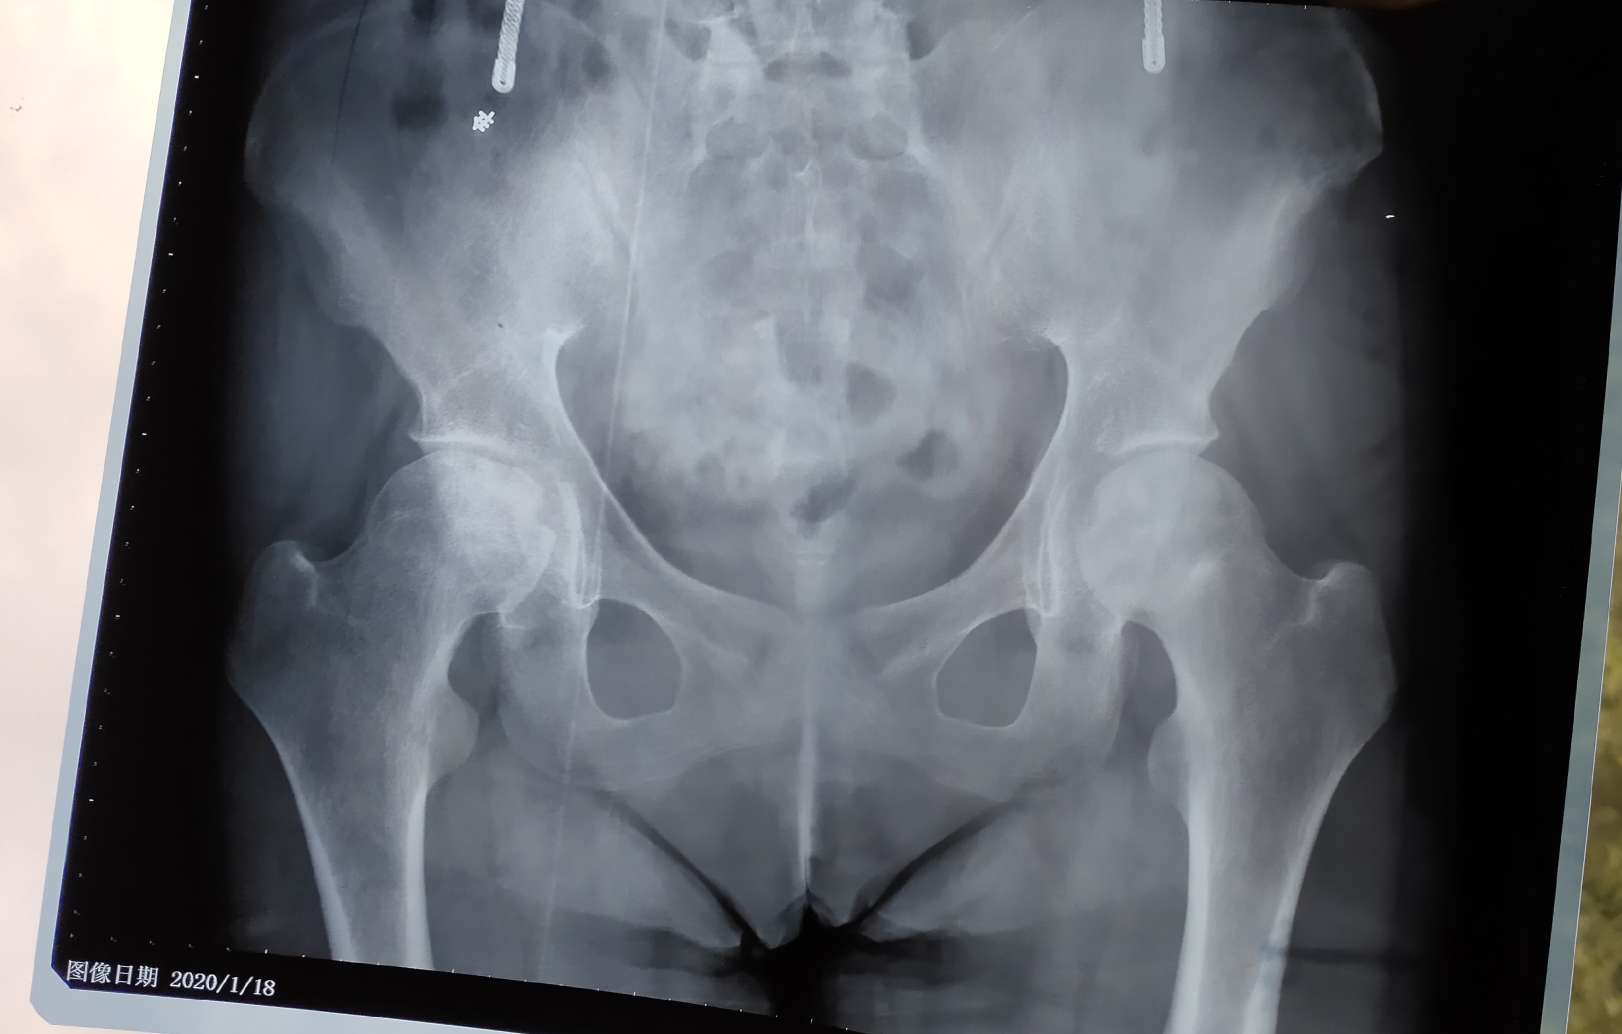

我才吃一年半激素,也双侧骨坏了。拍DR看不出来,复查再拍磁共振才看到。